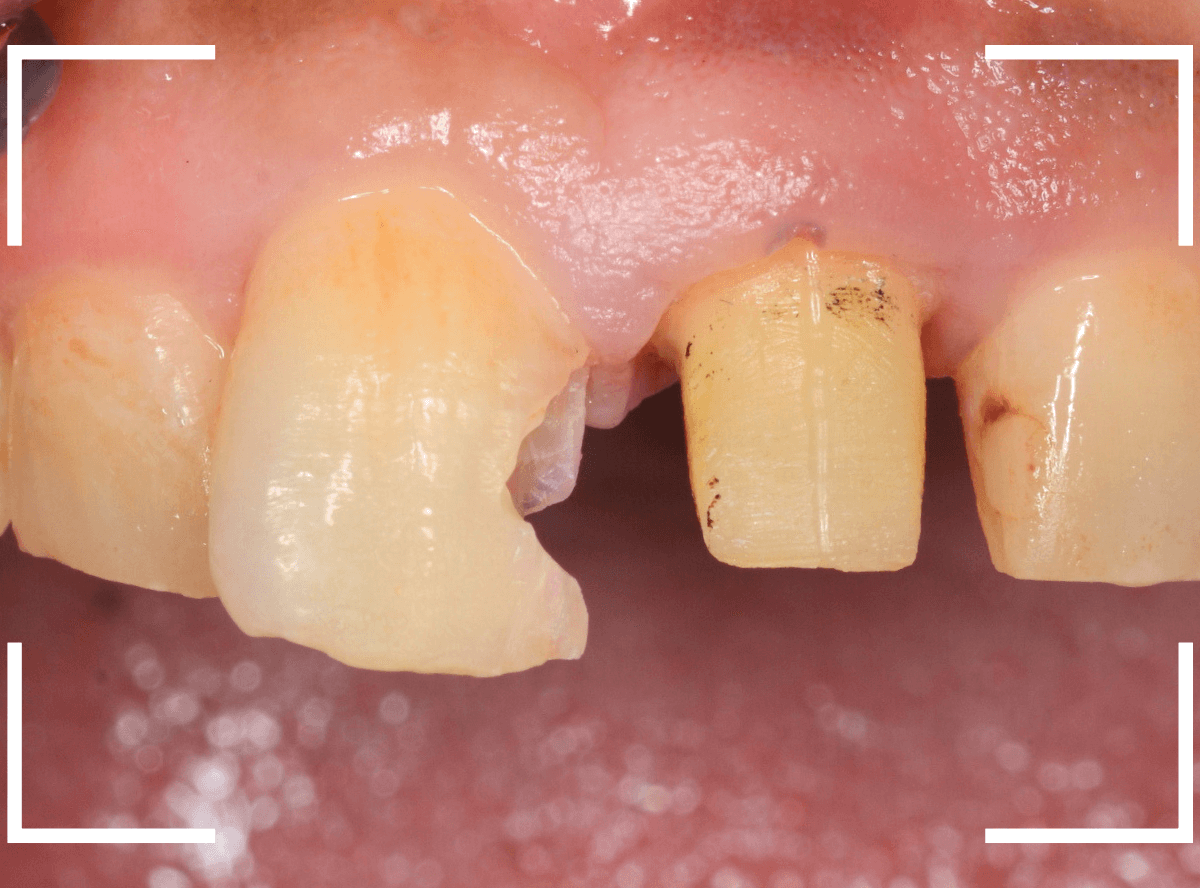

さし歯を外すと、金属の土台(メタル・コア)が出てきました。

慎重に土台を外して、中を調べます。

赤く染色されている部分が虫歯の残っているです。

慎重に虫歯を除去して、土台の型を取ります。